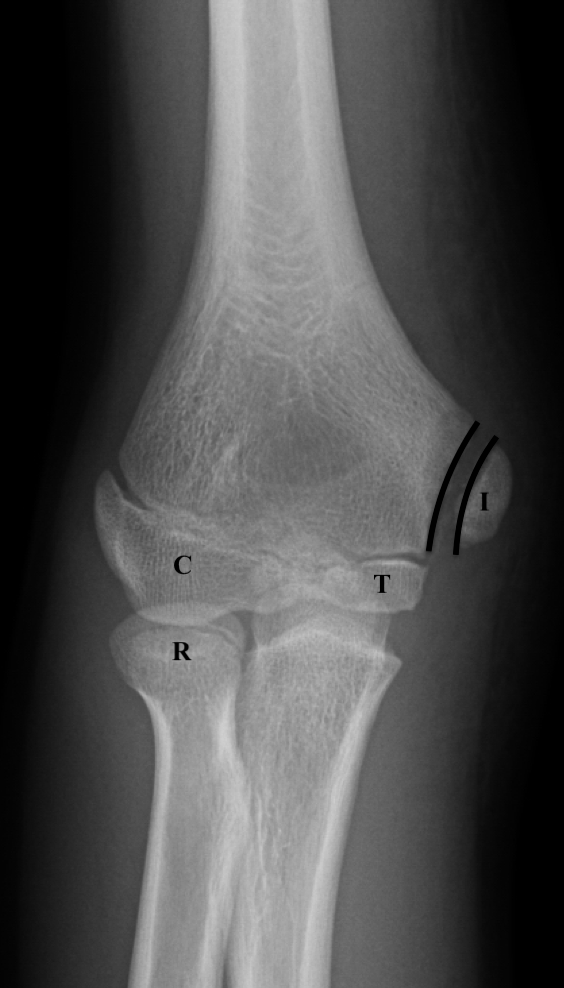

Оссификаты Локтевого Сустава: Диагностика и Лечение

Раздел: Секреты мастерства